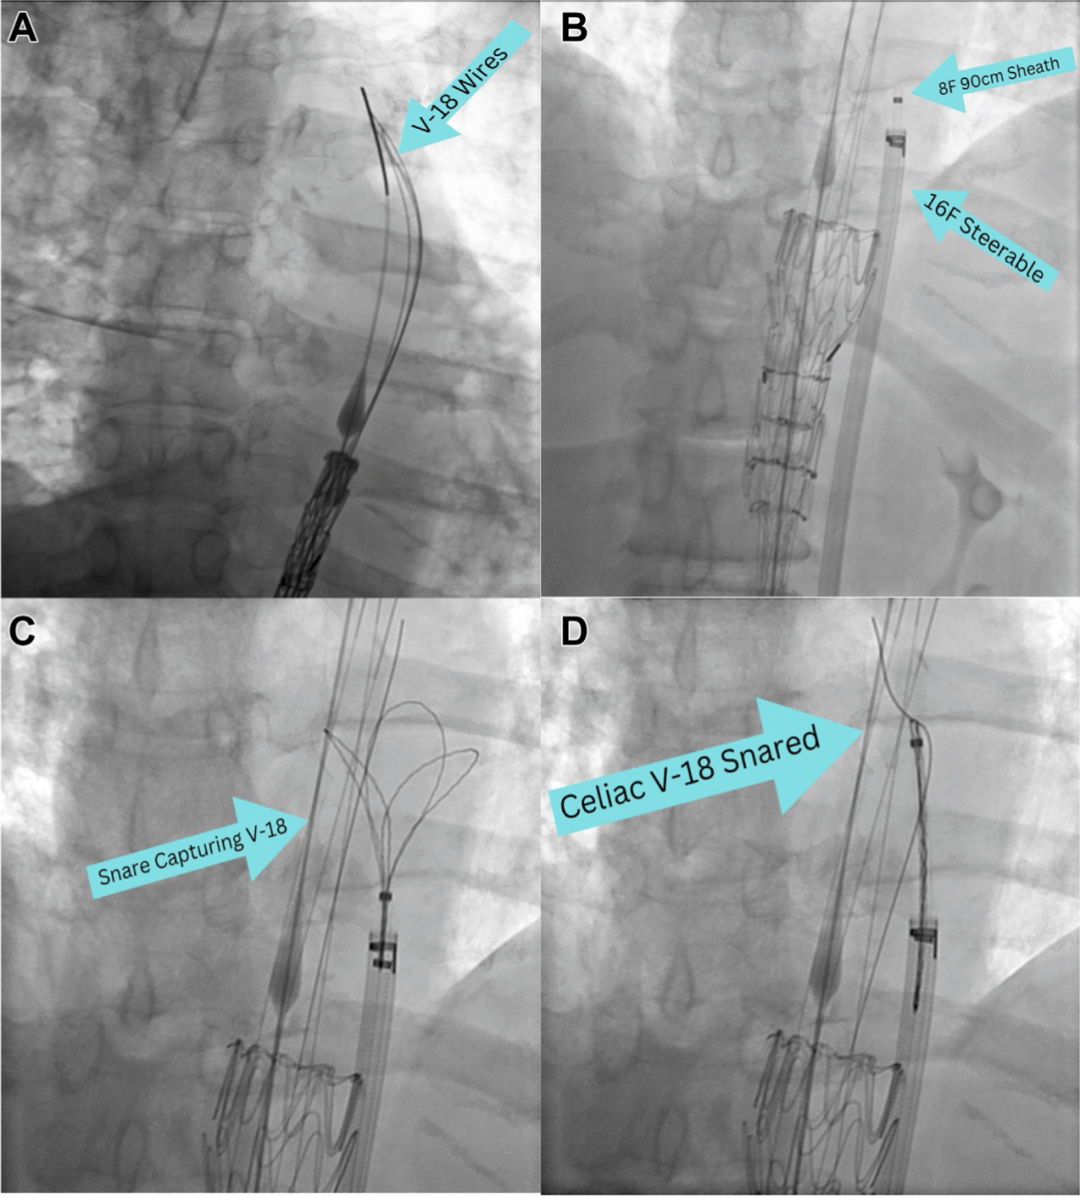

装置放置与建立贯穿导丝:胸腹分支腔内移植物(TAMBE)通过其分支口装载了四根V-18导丝,经由左股动脉入路沿一根硬导丝被推送至主动脉内(A)。将8 Fr鞘管置入16 Fr可调弯鞘管内,通过右股动脉入路将其放置在TAMBE装置旁,然后进行TAMBE的第一阶段释放(B)。通过8 Fr鞘管内的圈套器,捕获预先穿过腹腔干分支口的V-18导丝(C)。将V-18导丝拉出8 Fr鞘管,从而建立一根贯穿导丝(D)。

血管插管与支架输送:偏转可调弯鞘管,8 Fr鞘管沿着V-18导丝通过腹腔干分支口前进(A)。确认血管插管成功后,沿一根Rosen导丝将桥接支架定位在腹腔干动脉内(B)。完成TAMBE的第二阶段释放,扩张分支口;移除腹腔干内的贯穿导丝,然后释放腹腔干支架(C)。